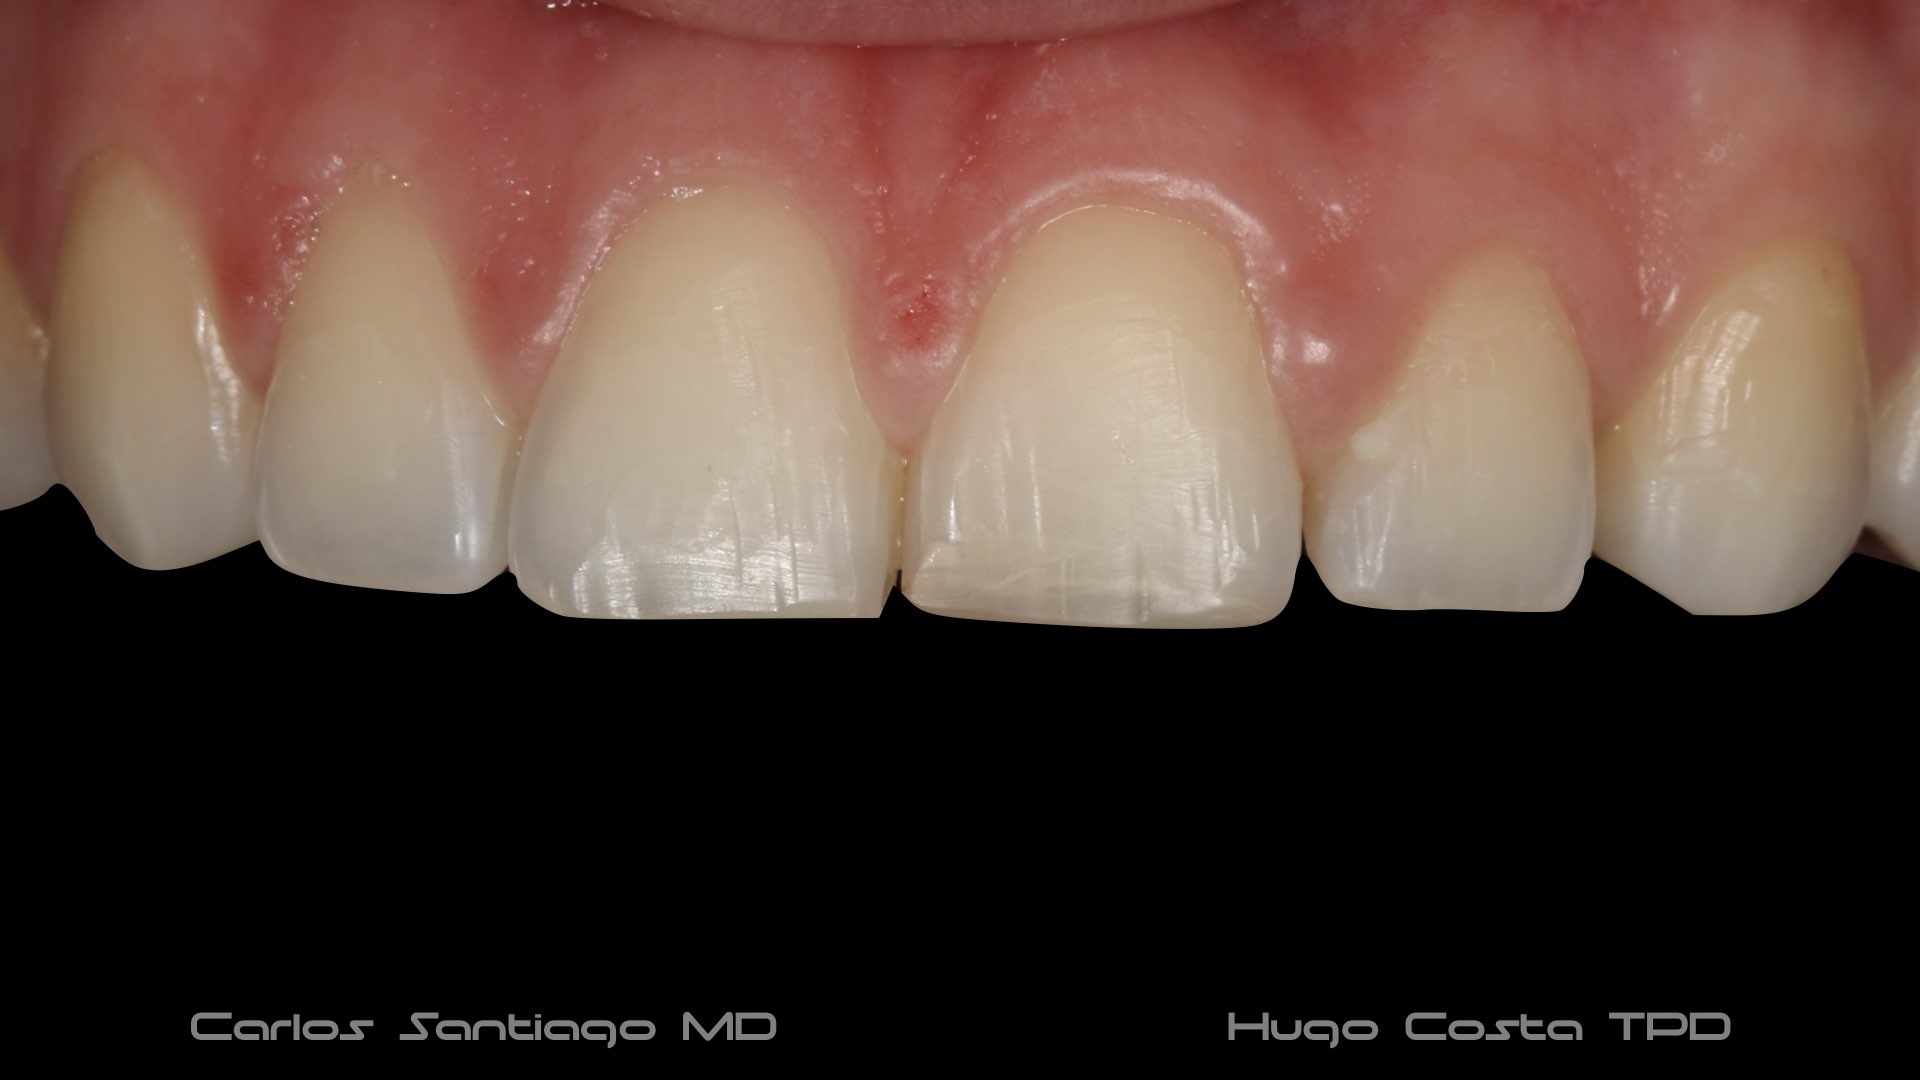

As Facetas Cerâmicas (lentes de contacto dentárias ou laminados), permitem corrigir da maneira mais estética e conservadora possível, problemas de forma e tamanho, côr e posição dos dentes, bem como substituir restaurações antigas e inestéticas.

São aderidas químicamente ao esmalte dentário de uma forma permanente, com o objectivo de melhorar a estética dos nossos pacientes.